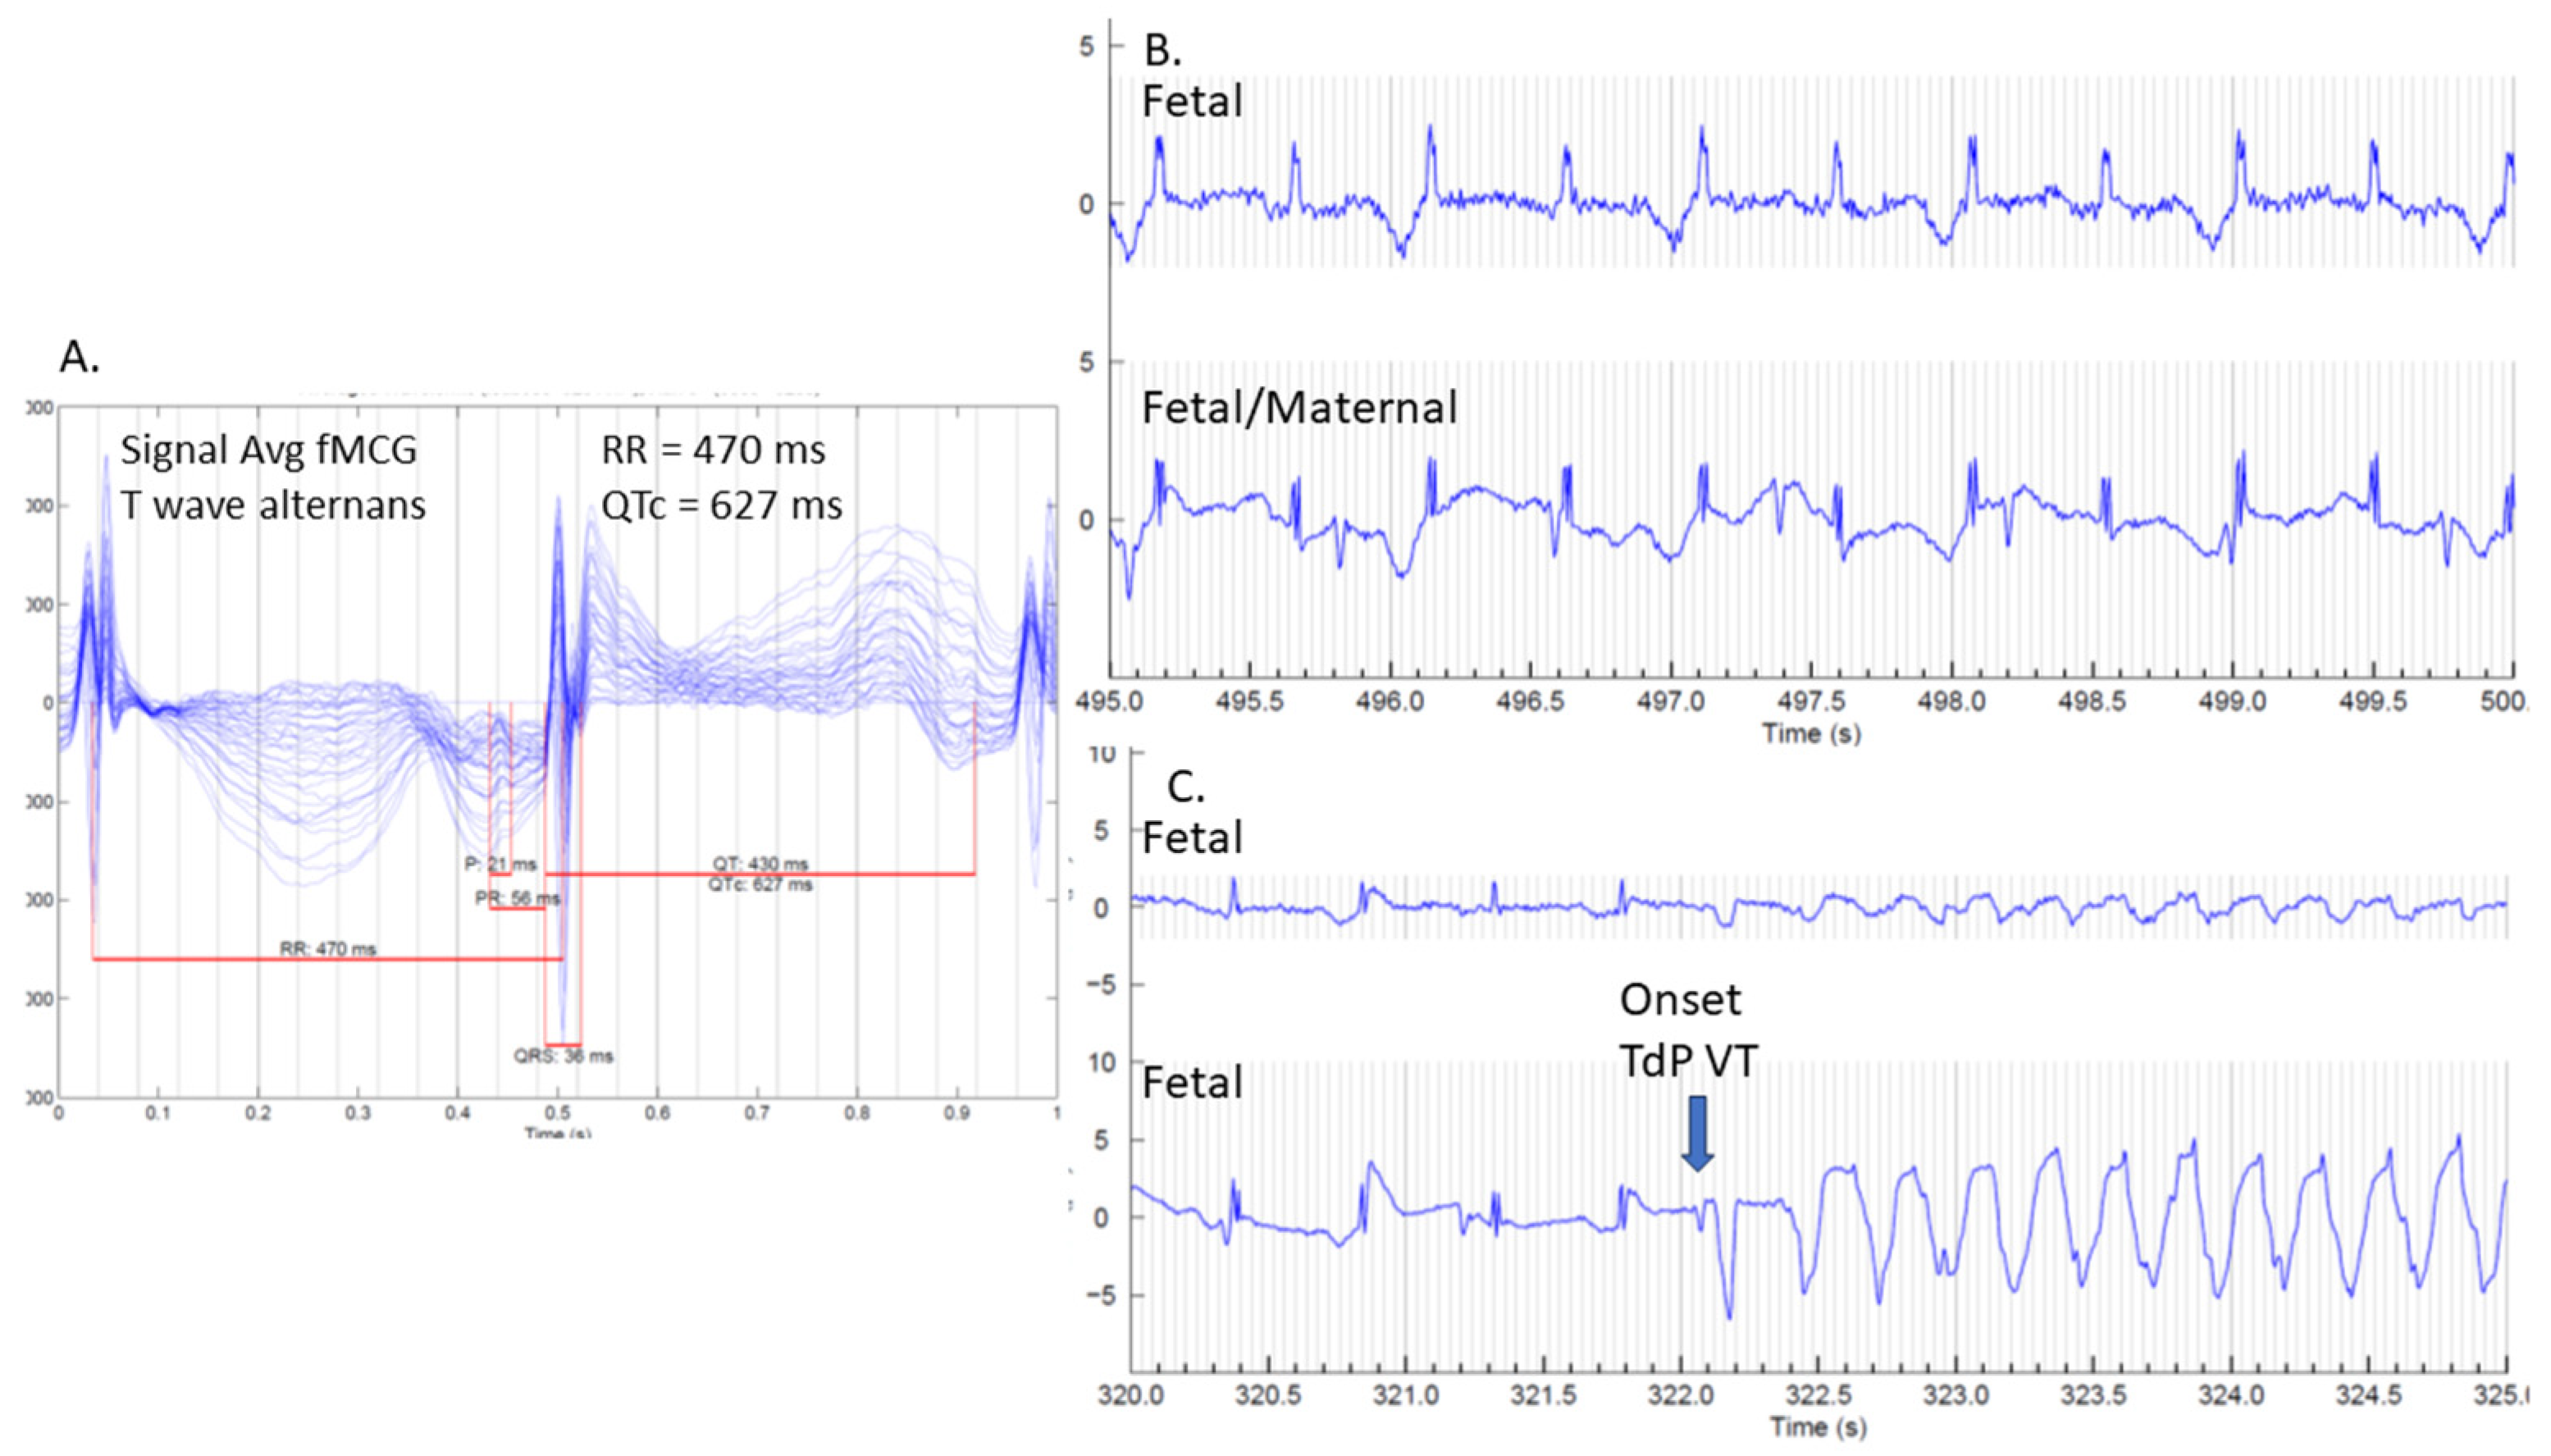

3. Utility of Fetal Magnetocardiography